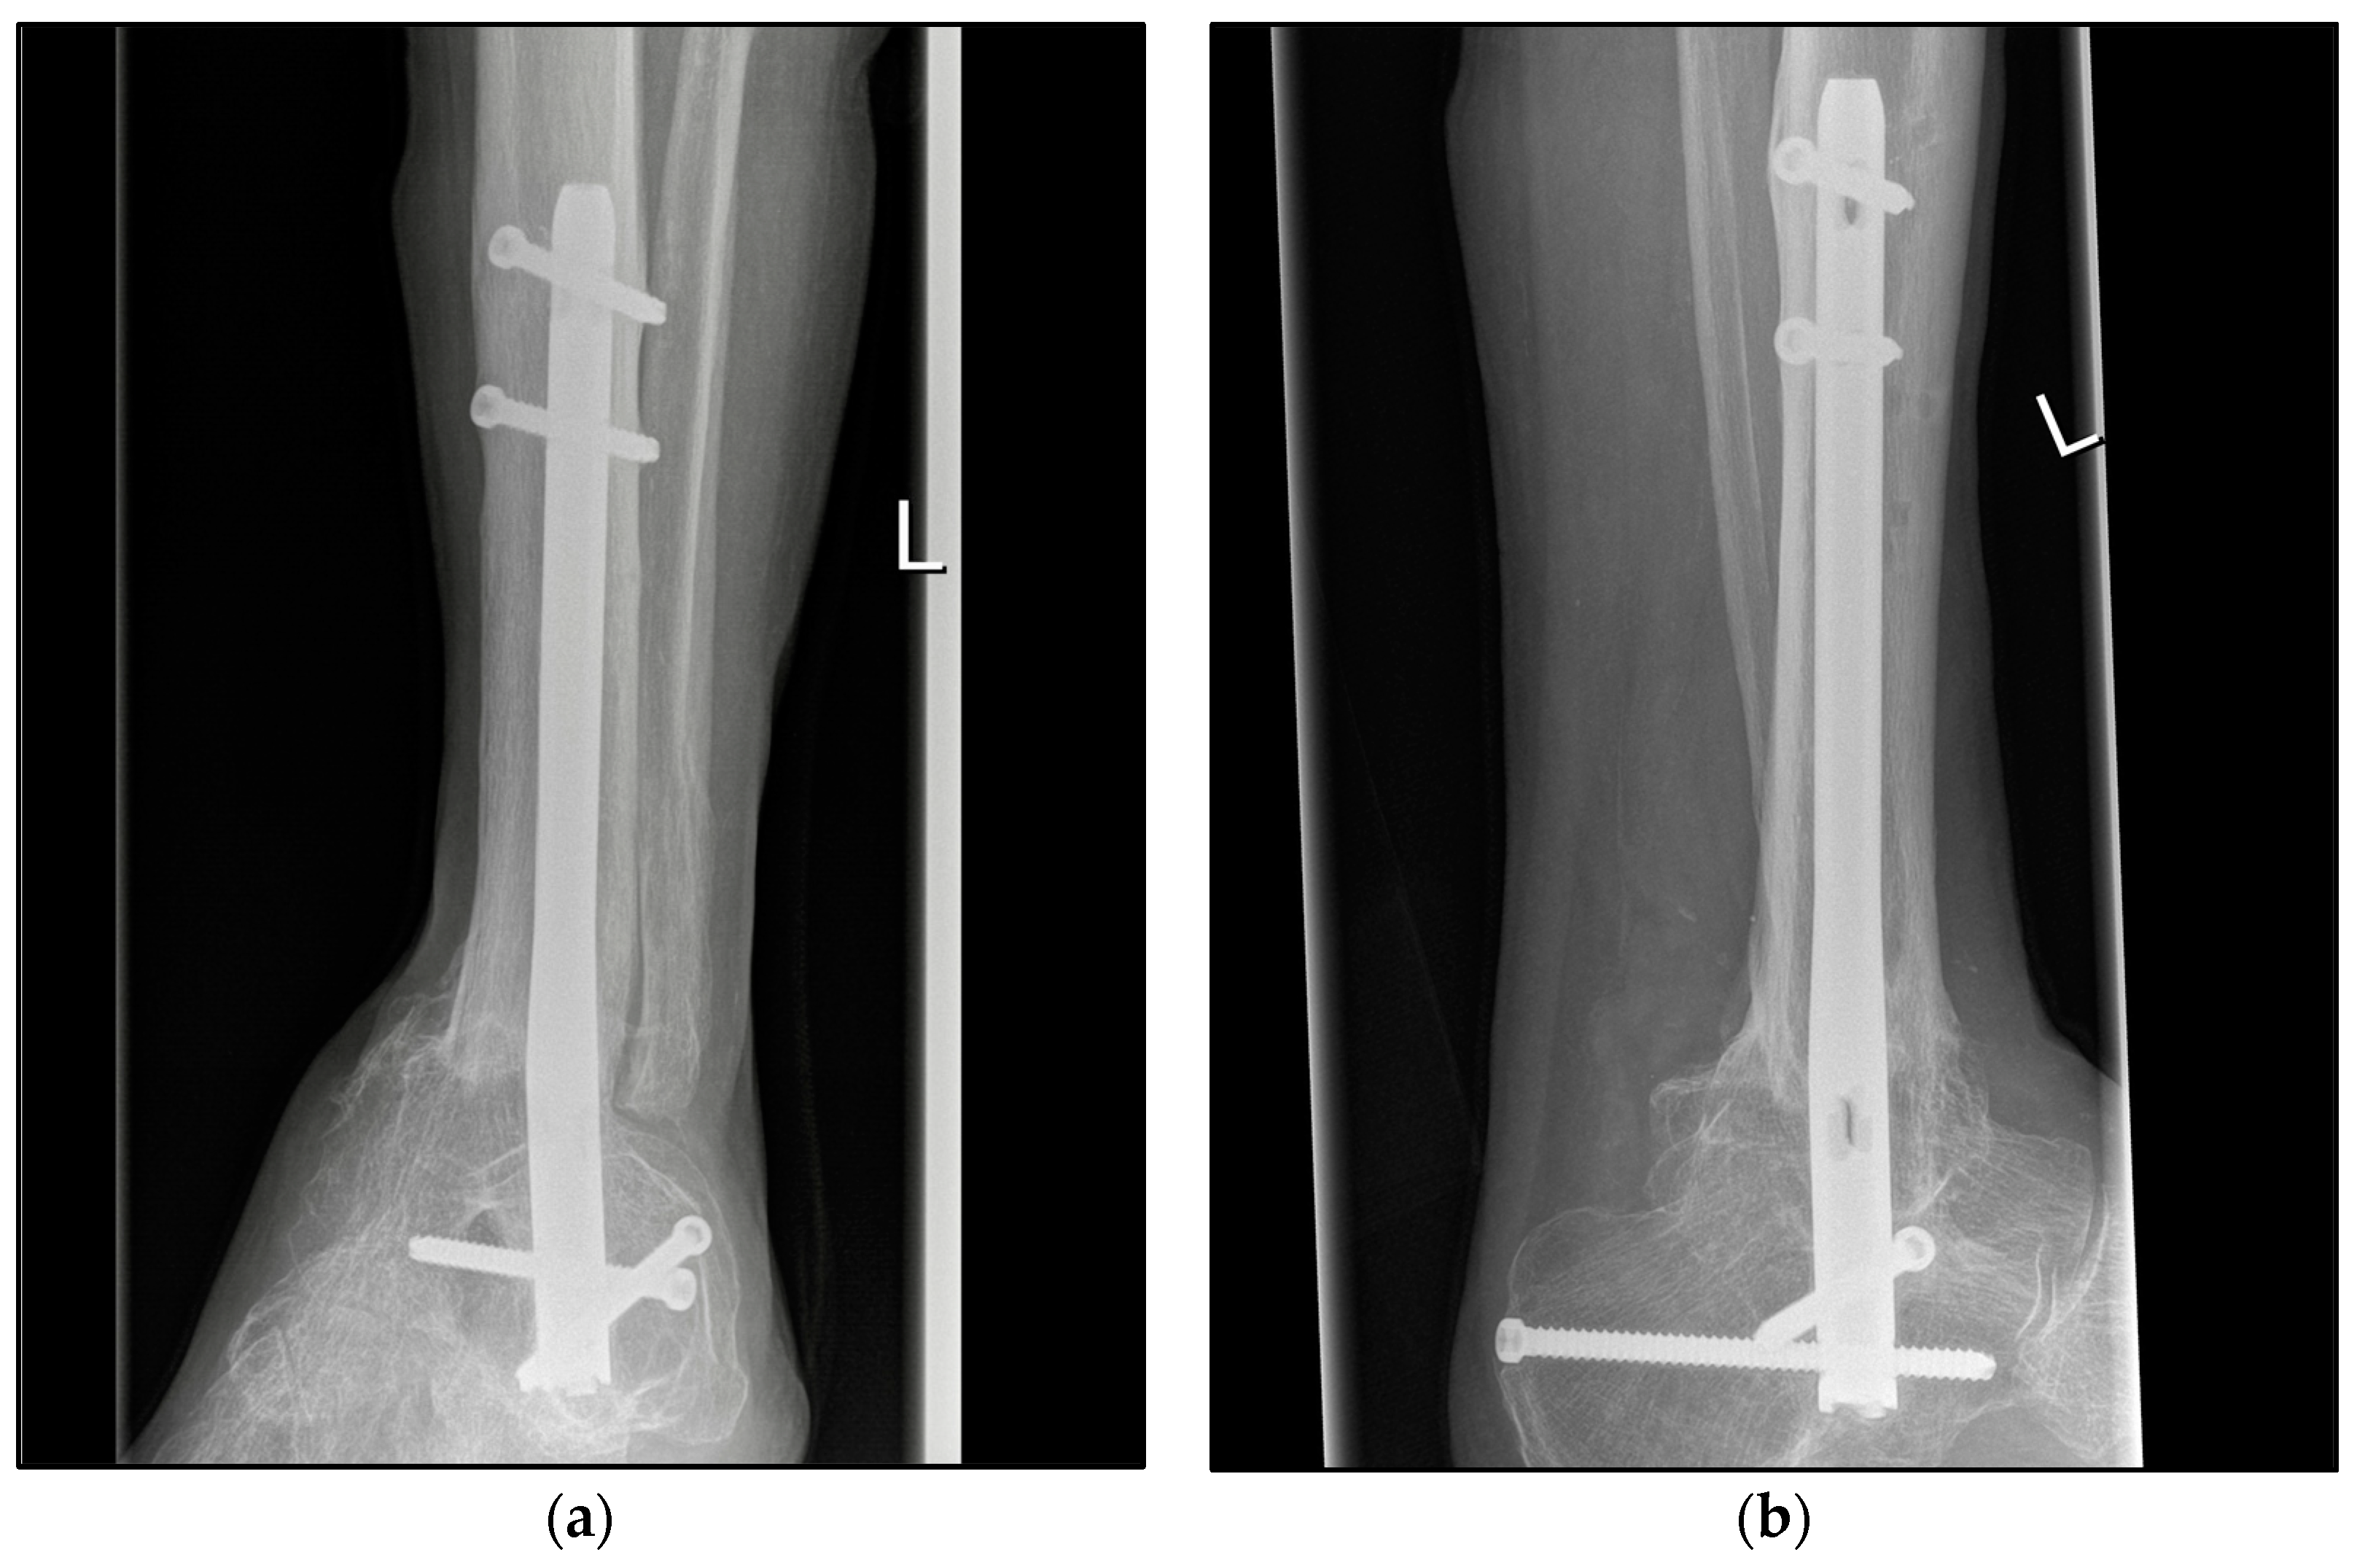

2.3. Surgical Procedure